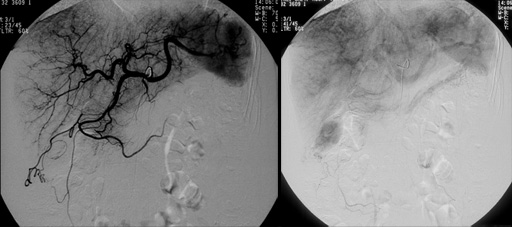

図3 図4 血管造影(腹腔動脈)

図4 血管造影(腹腔動脈)